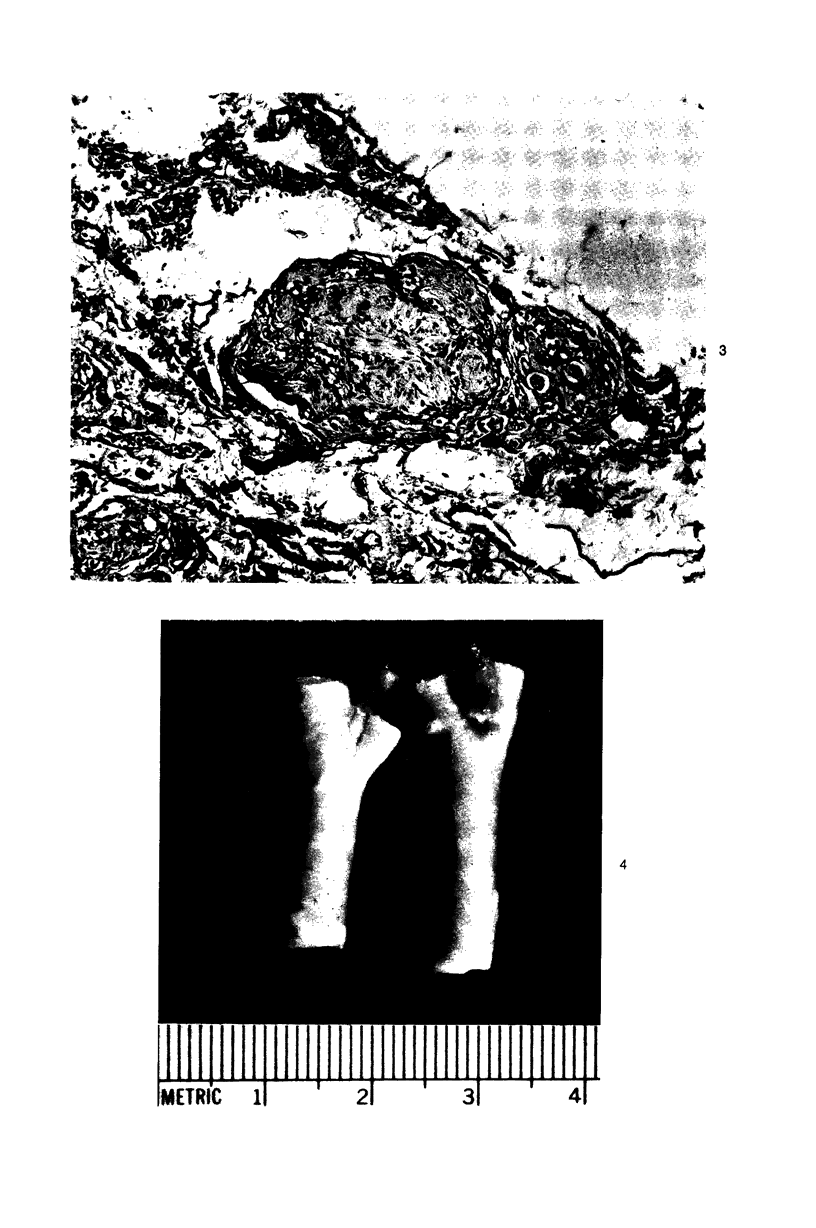

Vagal and carotid body paraganglia were obtained from 43 randomly selected autopsies performed at the National Naval Medical Center. In each case, tissue from both sides was step sectioned and comparatively studied. The mean combined weight of carotid bodies in 37 control patients was 25.9 mg. There was good correlation between size and number of separate paraganglia comprising the vagal body (seven left, six right). Lobules were closely related to the ganglion nodosum and were actually within it in three instances. Tissue resembling parathyroid was encountered within 4 of the 86 resected vagus nerves. Lymphocytic infiltration occurred in carotid and vagal body paraganglia of 28% and 16% of patients, respectively. There was Schwann cell proliferatation in carotid body lobules of 2 patients; in another patient, talc emboli were present. The mean combined weight of carotid bodies in 6 patients with chronic hypoxemia was 47.6 mg, significantly greater than in the control group; in each case, lobules were enlarged. Chief cell hyperplasia occurred in vagal body paraganglia of 2 patients; in two other patients, lobules were large with equal proliferation of constituent cells. These morphologic findings indicate that in patients with chronic hypoxemia some vagal body paraganglia can be ascribed a chemoreceptor role similar to but probably less important than that of the carotid body.

Images in this article